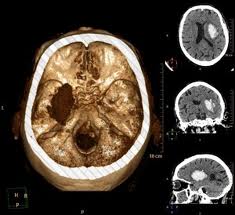

ДИАГНОСТИКА

Провести клиническое обследование (анамнез и неврологический осмотр). Достоверная диагностика кровоизлияния в мозг возможна на основании КТ или МРТ томографии. При отсутствии возможности проведения этих методов, диагностика менее достоверна и является результатом анализа клинической картины, данных спинномозговой пункции (в ликворе присутствует кровь), эхоэнцефалоскопии, дуплексного сканирования и церебральной ангиографии. Также необходимо исследовать: электролиты сыворотки крови, показатели функции почек, ЭКГ, маркеры ишемии миокарда, клинический анализ крови, протромбиновый индекс, насыщение крови кислородом.

Медицинские процедуры, проводимые при заболевании внутримозговое кровоизлияние: КТ головного мозга (КПП) сканирование без красителей, Магнитно-резонансная томография, Спинальная пункция, Эхоэнцефалография, Дуплексное сканирование брахиоцефальных артерий (БЦА), Ангиография, Биохимический анализ крови, ЭКГ, Клинический анализ крови, Протромбиновое время, Протромбиновый индекс, Исследование газов крови